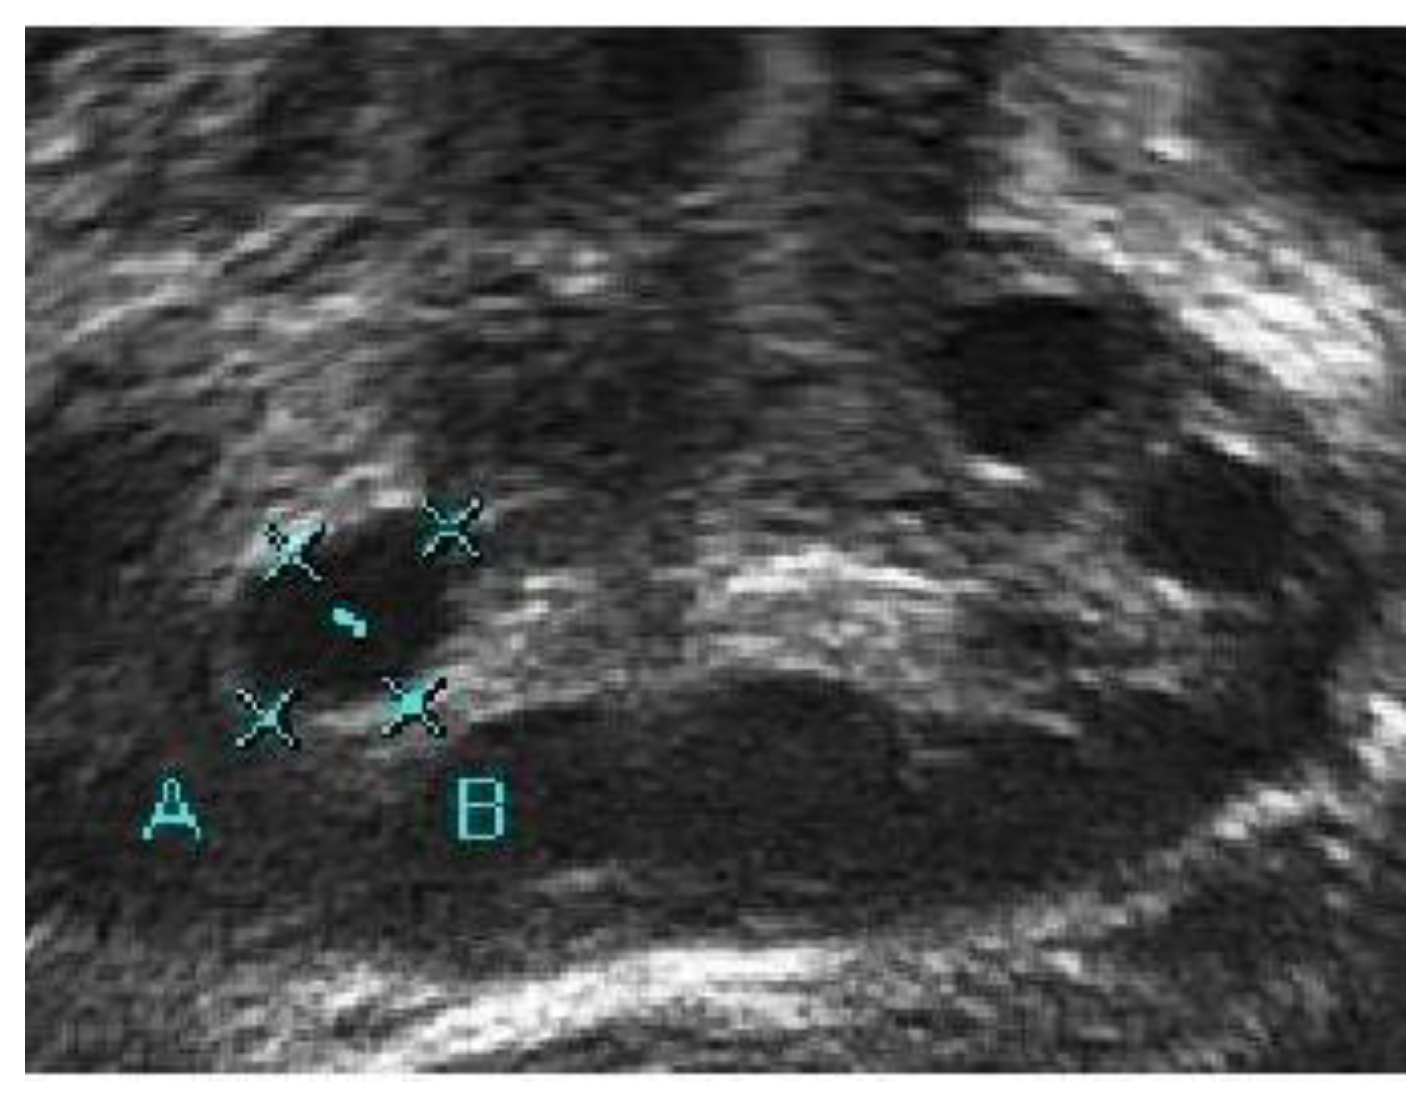

A medical expert was asked to mark the follicle boundary in the ultrasound image to be the ground truth, because this study will be implemented on local ultrasound images. Figure 7 shows the original ultrasound images that were collected by medical experts during patient monitoring, and Figure 8 shows the ultrasound images marked with red circles by medical experts to highlight the existing follicles.

Figure 7.

Original ultrasound acquired from the HCTM MAC unit.

Figure 8.

Image of identified follicles marked by medical expert.